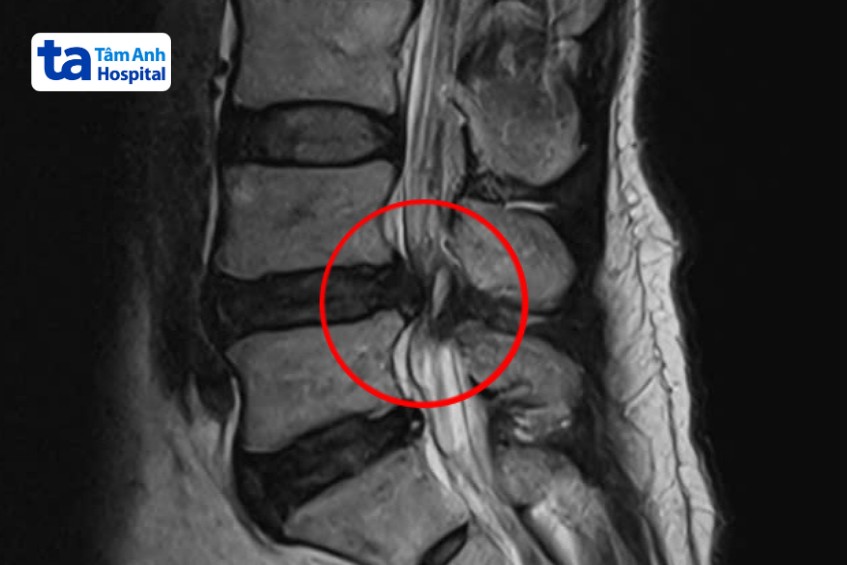

Ngày 24/3, BS.CKI Nguyễn Văn Toại, khoa Cột sống, Trung tâm Chấn thương Chỉnh hình, Bệnh viện Đa khoa Tâm Anh TP HCM, cho biết kết quả chụp MRI cho thấy ông Chính bị trượt, hẹp ống sống ở đốt sống lưng L4, L5. Tình trạng này kéo dài nhiều năm, chèn ép dây thần kinh, gây đau đớn nhiều và khó đi lại. Nếu phẫu thuật càng trễ, hiệu quả phục hồi sẽ càng giảm. “Người bệnh đang đối mặt tình trạng yếu cơ, tổn thương thần kinh, dẫn đến yếu liệt, rối loạn tiêu tiểu…”, bác sĩ Toại đánh giá.

Hẹp ống sống là tình trạng không gian bên trong ống sống bị thu hẹp, gây áp lực lên các rễ thần kinh, tủy sống đi qua cột sống. Trong khi đó, trượt đốt sống là tình trạng đốt sống trên trượt ra phía trước hoặc ra phía sau so với đốt sống dưới. Những bệnh lý này gây đau và làm giảm khả năng vận động của người bệnh.